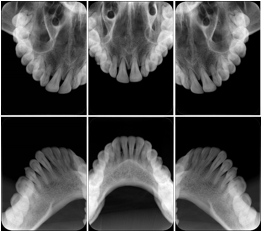

Intra-oral radiography typically involves acquisition of multiple images of various parts of the dentition. Many digital radiographic systems offer customized templates that are used for displaying the images in a study on the screen. These templates may also be referred to as mounts or view sets. The Structured Display Object represents a standard method of encoding and exchanging the layout and intended display of Structured Displays. A structured display object created in this manner could be stored with a study and exchanged with images to allow for complete reproduction of the original exam.

3. A dental provider wishes to capture a series of DICOM IO images for the patient’s dentition. The tooth morphology, teeth are divided into molars, premolars, canines and incisors, and a number of images for each jaw. The anatomic information was captured utilizing the triplet of schema. This standard code sequence is based on ISO 3950-2010, Dentistry - Designation system for teeth and areas of the oral cavity.

In most standard cases, images are oriented in structured layouts. These structured displays are useful to be shared between providers for reference purposes.

Table OO.1.1-1 shows structured display standard templates, where Viewset ID is based on the Japanese Society for Oral and Maxillofacial Radiology (JSOMR) classification provided by JIRA (Japan Medical Imaging and Radiological Systems Industries Association, www.jira-net.or.jp). Expected or typical teeth to be imaged location, region and designation codes are based on ISO 3950-2010, Dentistry - Designation system for teeth and areas of the oral cavity. For all the hanging protocols listed in OO.1.1-1, the value to use for Hanging Protocol Creator (0072,0008) is "JSOMR" and the value to use for Hanging Protocol Name (0072,0002) does not include "JSOMR" (e.g., "DL-S001A", not "JSOMR DL-S001A").